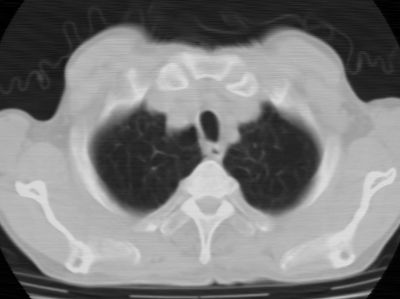

标题: CT24783:m71,既往肺心病史3年,现咳嗽,憋喘。 [打印本页]

标题: CT24783:m71,既往肺心病史3年,现咳嗽,憋喘。

2、全小叶性肺气肿。

1)左肺上叶周围型肺癌可能。2)两肺全小叶型肺气肿。